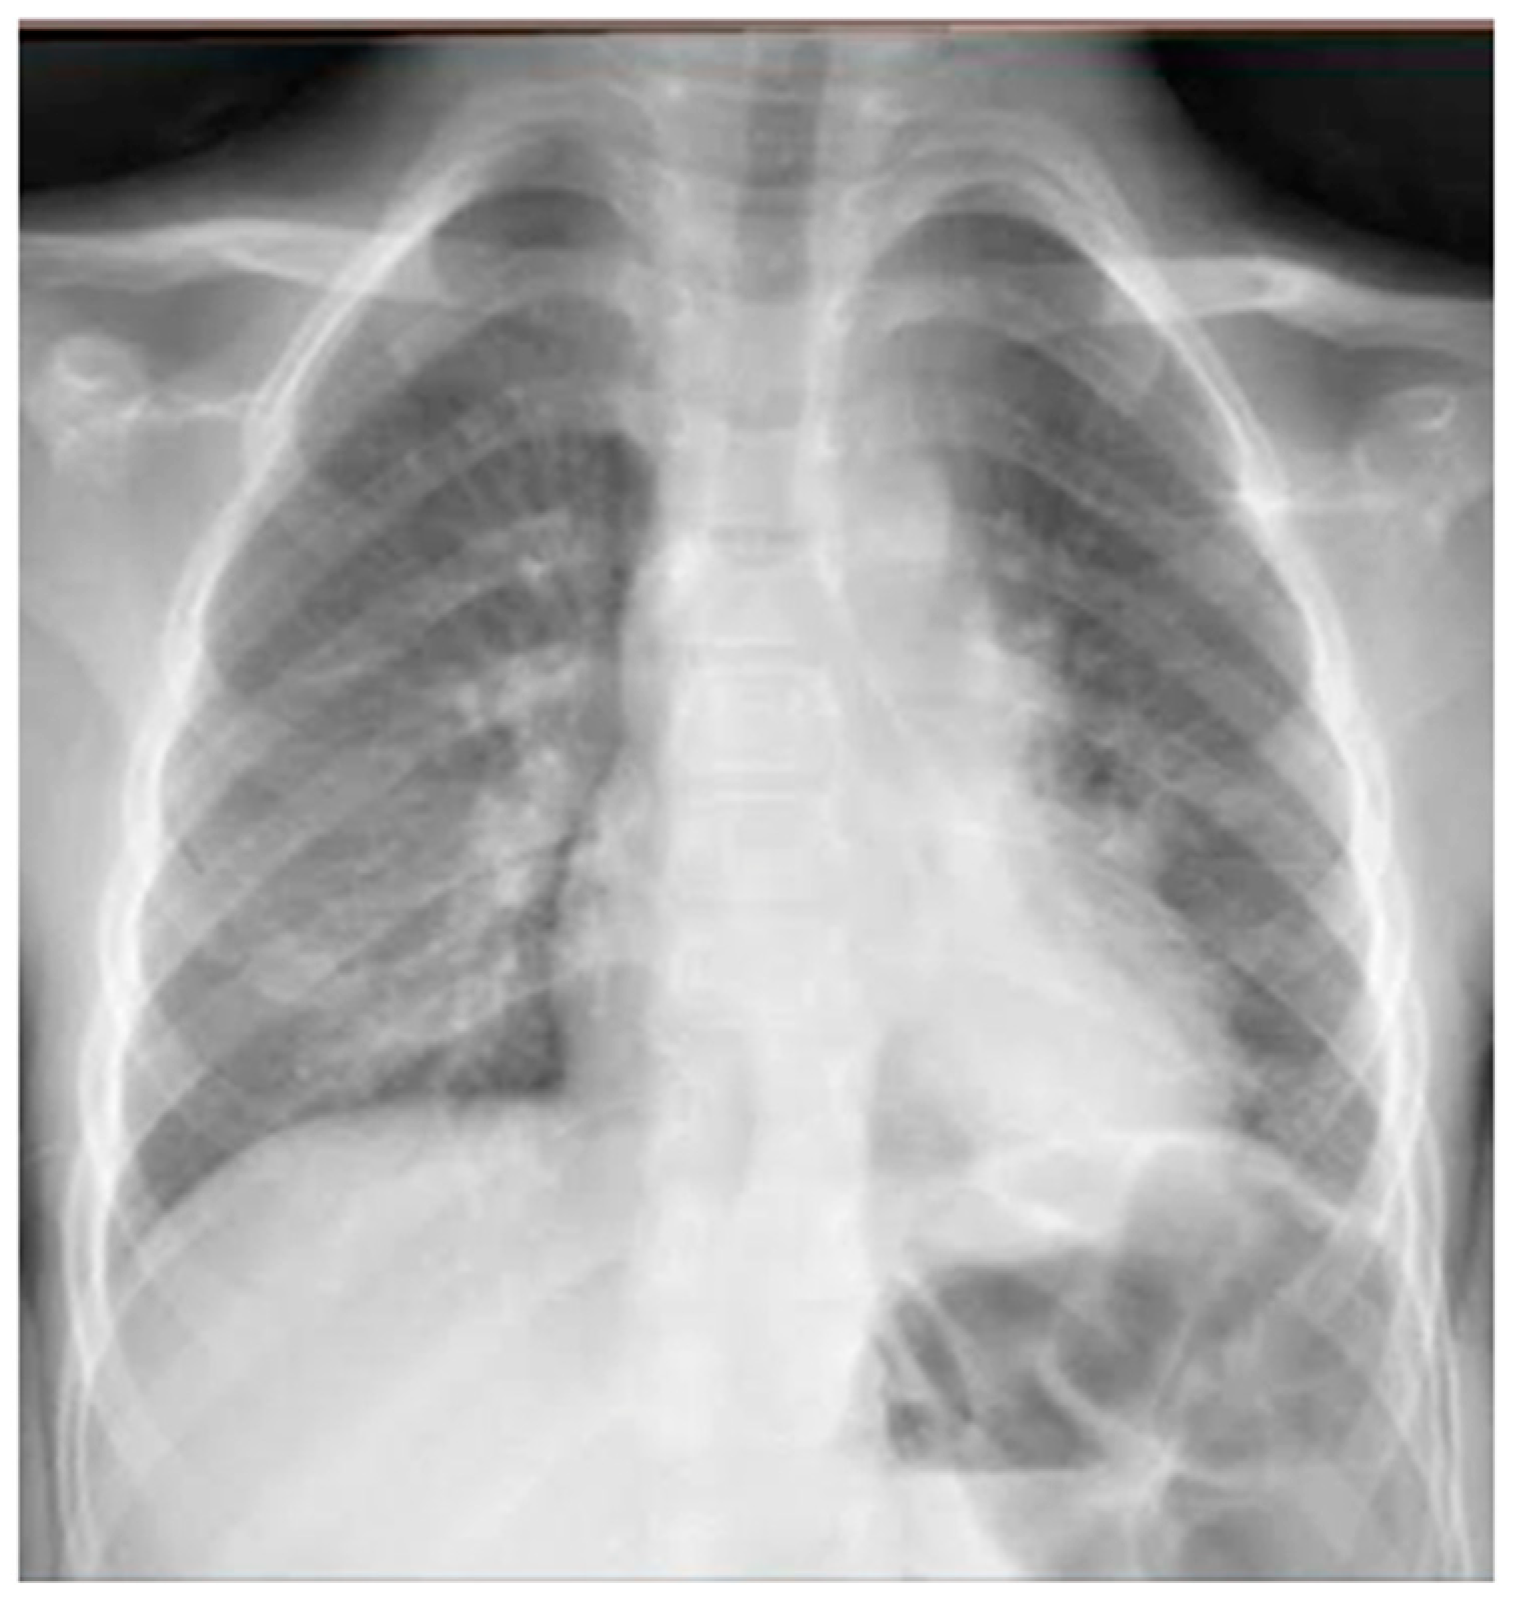

She was moderately dyspneic, in good general condition, and with stable vital signs. She had a slight rise in the indexes of inflammation. At the PED, a chest X-ray was performed to exclude an infectious picture in consideration of the auscultator finding of reduced air penetration in the right hemi thorax. The radiographic picture (Figure 4) was interpreted as an inflammatory type consolidation. Therefore, therapy for acute asthma attack and antibiotic therapy was set up, and she was hospitalized in the pediatric ward. Here, at the same time as the clinical evaluation, we performed LUS, which showed the presence of a picture of SIS, and several areas of lung atelectasis, one of which involved the middle lobe—localized in the right anterior mid-apical area (paracardiac) (Figure 5). The LUS picture was highly positive, but excluded the presence of inflammatory/infectious consolidations. On the basis of these data, the antibiotic therapy was therefore suspended, high flow oxygen therapy was set in consideration of the presence of atelectasis areas, and therapy of the moderate–severe acute attack was continued with subsequent suspension of respiratory support after about a week of therapy. Furthermore, the microbiological investigations of the airways were positive for adenovirus. An adequate preventive therapy was set up [1,2,3]. LUS follow-up showed a complete resolution of the areas of atelectasis after 2 weeks from the start of preventive therapy, and of the SIS after about 4 weeks from the start of the therapy itself.

Chest radiography shows, on the right fields in the apical and basal areas, a non-specific area of reduced transparency. It also shows signs of interstitial engagement in the para-hilar position bilaterally.